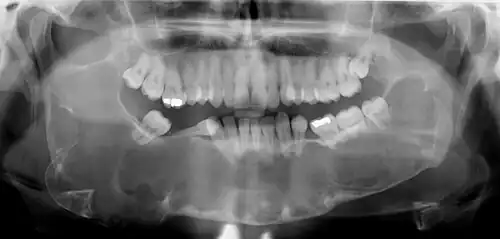

Classic look of an odontogenic keratocyst of the right mandible in the place of a former wisdom tooth. Well defined, unilocular, radiolucent lesion within the bone.

Diagnosis is usually radiological. However, definitive diagnosis is through biopsy. Aspirational biopsy of odontogenic keratocysts contains a greasy fluid which is pale in colour and contains keratotic squames.[13][2] Protein content of cyst fluid below 4g% is diagnostic of odontogenic keratocysts.[2] Smaller and unilocular lesions resembling other types of cysts may require a biopsy to confirm the diagnosis.[10] On a CT scan, the radiodensity of a keratocystic odontogenic tumour is about 30 Hounsfield units, which is about the same as ameloblastomas. However, ameloblastomas show more bone expansion and seldom show high density areas.[14]

Radiographs of odontogenic keratocysts show well-defined radiolucent areas with rounded or scalloped margins which are well demarcated.[13] These areas can be multilocular or unilocular. The growth pattern of the lesion is very characteristic from which a diagnosis can be made as there is growth and spread both forward and backward along the medullary cavity with little expansion. No resorption of teeth or inferior dental canal and minimal displacement of teeth is seen. Due to lack of expansion of the odontogenic keratocyst, the lesion can be very large when radiographically discovered.[10]